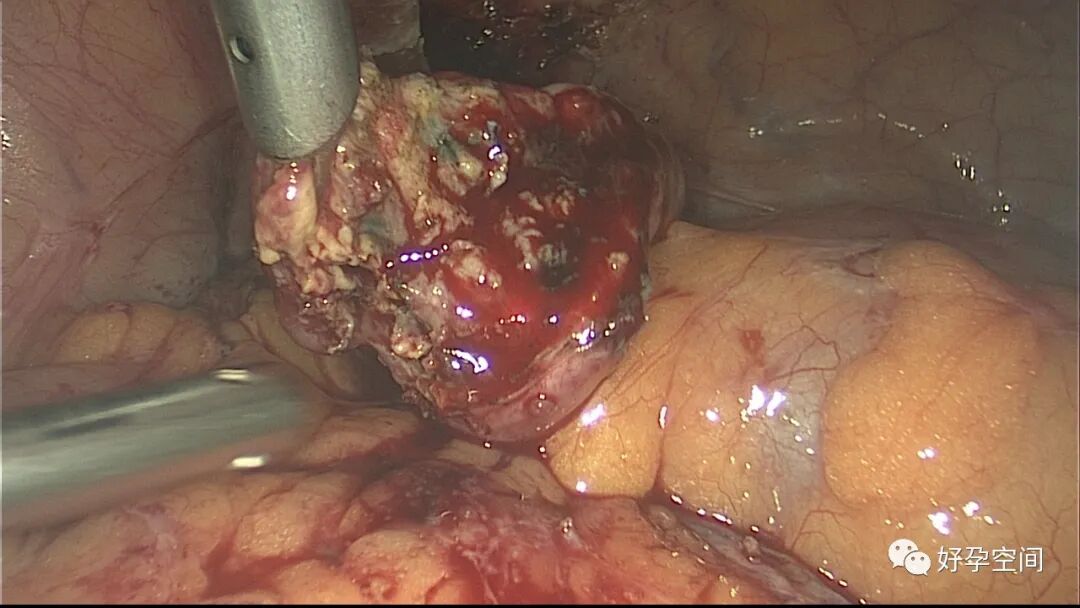

病例1:患者24岁,原发不孕,造影示双侧输卵管堵塞,否认结核病史,无结核病家族史。2022年4月以不孕症收入院手术,术前化验检查无明显异常,胸片示左肺下叶内带稍高密度结节影。行宫腹腔镜探查,宫腔被覆一层棉絮状质脆增生组织,宫腔狭小,宫壁僵硬。腹膜及大网膜广泛分布粟粒样结节,左侧输卵管充满干酪样组织及灰色脓液。

子宫内膜结核是由结核分枝杆菌在子宫内膜部位种植引起的炎症,是仅次于输卵管结核的常见女性生殖器结核。子宫内膜结核常由输卵管结核蔓延而来,多继发于盆腔腹膜结核或肺结核。子宫内膜结核的超声表现主要为:子宫内膜回声不均匀、宫腔内结节样病灶、宫腔内强回声灶、单纯的子宫内膜薄等。盆腹腔超声显示输卵管炎性表现:输卵管增粗、肥厚、扭曲、僵硬、输卵管积液积脓、卵巢旁混合性包块、输卵管系膜囊肿、盆腔包裹性积液等。术中所见:盆腹腔组织粘连、盆腹腔粟粒样结节、结核球、脓肿等,输卵管伞端烟斗样外翻,输卵管内充满淡黄色干酪样或豆渣样组织。宫腔镜显示宫腔狭窄、宫壁僵硬、宫内膜肉芽肿样增生、内膜质脆易刮除、干酪样组织、脓液等。